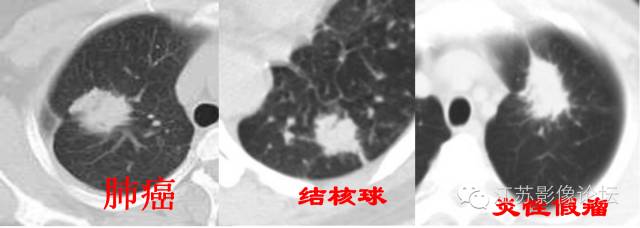

弦距与距长之比>2/5为深分叶;肺癌常见深分叶,错构瘤及结核球可呈浅分叶;炎性假瘤多呈不规则形状。

约90%毛刺结节为恶性结节,部分良性结节边缘也可见毛刺,多为长毛刺及“尖角征”。

最常见于错构瘤和结核球;错构瘤30%有爆米花样钙化,结核球常见弧形或环形钙化;而砂粒状钙化常见于恶性结节,但很少见。